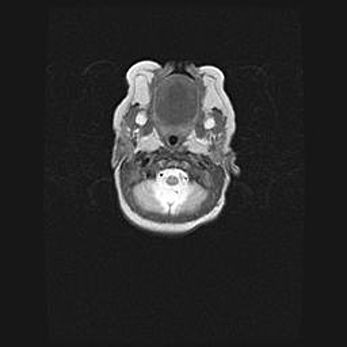

Мальформация Денди-Уокера. Киста задней черепной ямки.

Агенезия мозолистого тела.

Возраст: 2,5 месяца

Вес: 2420 г

Пол: женский

Окружность головы: 37 см

Срок гестации: 32 недели

Мальформация Денди—Уокера — редкий вид патологии ЦНС, представляющий собой врожденный порок развития каудального отдела ствола и червя мозжечка, ведущий к неполному раскрытию срединной (Мажанди) и латеральных (Лушка) апертур IV желудочка мозга. Для этогно синдрома характерна триада симптомов: гипотрофия червя мозжечка и/или полушарий мозжечка, кисты задней черепной ямки, гидроцефалия различной степени. В 70% случаев порок сочетается и с другими аномалиями головного мозга, в частности с агенезией мозолистого тела.